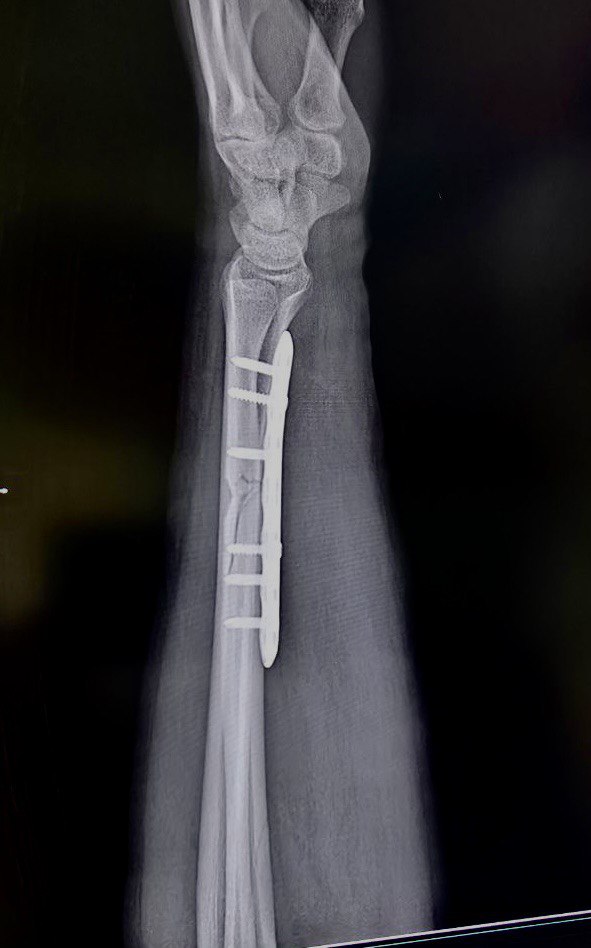

Клинический случай: внутрисуставной перелом дистального метаэпифиза лучевой кости — после операции

Контрольный осмотр и ранний послеоперационный результат.